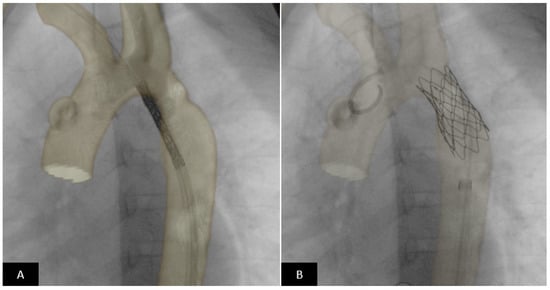

- Valverde, I.; Gomez, G.; Coserria, J.F.; Suarez-Mejias, C.; Uribe, S.; Sotelo, J.; Velasco, M.N.; Santos De Soto, J.; Hosseinpour, A.R.; Gomez-Cia, T. 3D printed models for planning endovascular stenting in transverse aortic arch hypoplasia. Catheter. Cardiovasc. Interv. 2015, 85, 1006–1012. [Google Scholar] [CrossRef] [PubMed]